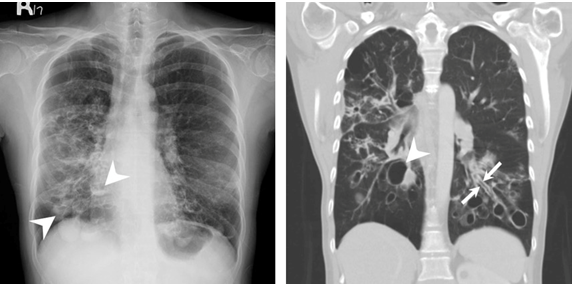

下肺可见增厚的支气管壁相互平行,管径一致,形成典型的双轨征(长箭头)

图2ct横断面示右下肺支气管扩张,部分显示轨道征(箭头)三,支气管碘油

细节显示右肺上叶柱状支气管扩张而呈现的轨道征( 箭头);c.